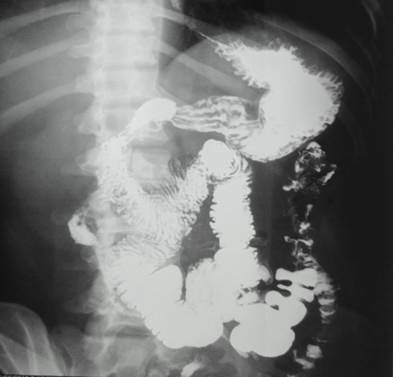

Liquido inflamatorio libre en cavidad, isquemia intestinal masiva desde el duodeno a colon transverso en un paciente (Imagen 1), desde una porción de aproximadamente 15 cms del ángulo de treitz a colon transverso en el segundo paciente (Imagen 2), en el tercero encontramos gangrena intestinal desde 10 cms del ángulo de treinta hasta la mitad del colon transverso derecho (Imagen 3).

Ilustración 2 Isquemia intestinal masiva

Fuente: Hospital de Especialidades Guayaquil “Doctor Abel Gilbert Pontón”.

Autor: Dr. Fernando Moncayo A.

Se verifico el tránsito corto mediante estudio de tránsito baritado intestinal (Imagen 7,8.9)

Ilustración 8 Tránsito gastro-intestinal postquirúrgica, muestra anastomosis yeyuno-colónica.